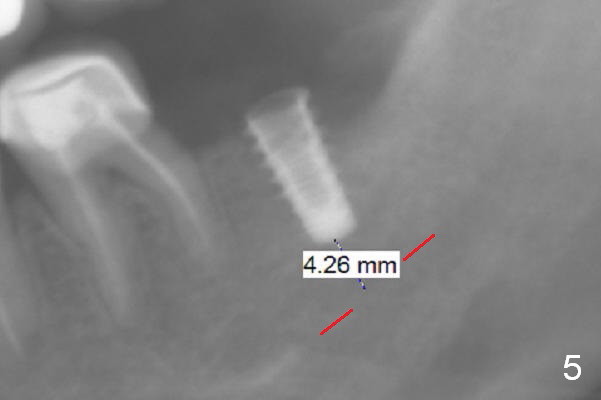

After 1.6 mm pilot drill (Fig.2) and 4.3 mm Magic Drill for 11 mm (gingival margin), a 4.5x11 mm dummy implant is placed with stability (Fig.3). Following Final Drill for 12/13 mm and 4.3 mm MD mesially, a 5x9 mm IBS implant is placed with 40 Ncm (Fig.4). Panoramic X-ray shows the placement is slightly supracrestal (Fig.5). In fact the implant is also placed slightly lingually. When the trajectory is changed, the implant loses stability. When a 5.5x9 mm implant is placed, no stability is achieved (Fig.6). After increase in osteotomy depth for 1-2 mm with MD 4.3 mm, the 5.5x9 mm implant barely obtains stability (~ 10 Ncm, Fig.7). Healing screw is placed. Osteogen plug is inserted in the distal portion of the socket; autogenous bone around the implant and Collagen plug to close the socket opening. Last suture and periodontal dressing are applied.